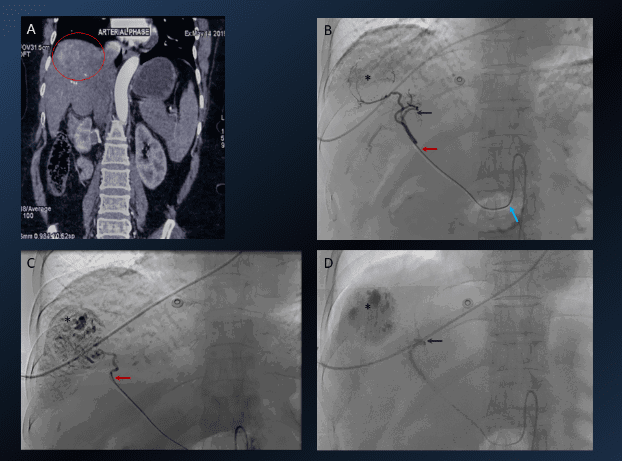

8. Giant hepatic hemangioma embolization

Giant hepatic hemangioma embolisation IR

Young lady with incidentally detected hepatic hemangioma while undergoing infertility evaluation. The patient is married for 3 years and wants to start infertility treatment and conceive. Hemangiomas are known to enlarge during pregnancy, which may rupture causing torrential haemorrhage. Surgical resection was not considered in view of large size and potential complications. A. Selective common hepatic arteriogram: large mass lesion(*) with supply from right hepatic artery (RHA) branches. Contrast puddling, akin to arterial phase CECT suggestive of hemangioma is seen (arrows). B. Glue embolization of the feeder artery done. C. Radio-opaque glue cast is seen in the RHA and its branches supplying the hemangioma (arrow). D. Post embolization angiogram showed complete non-opacification of the hemangioma with the preserved flow into the rest of the branches. GDA: Gastroduodenal artery, LHA: Left hepatic artery On 3 months follow up there was absent vascularity noted on Doppler examination with stable size. The patient went back on infertility treatment.